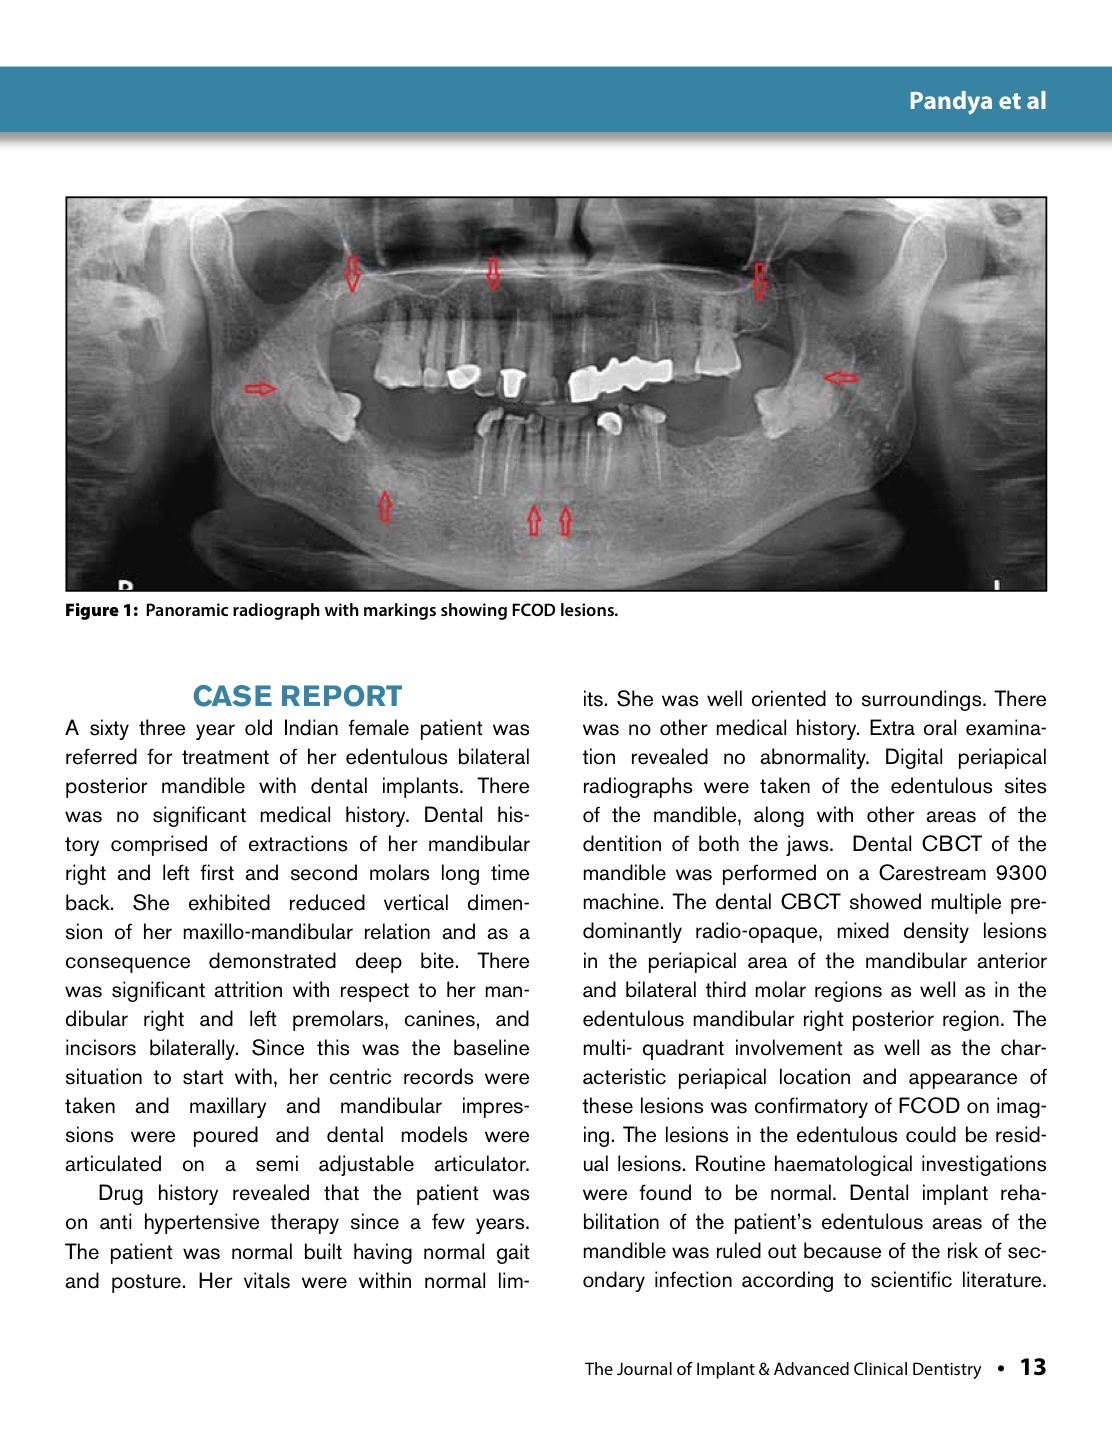

Journal of Implant and Advanced Clinical Dentistry September 2014 Implant Dentistry Journal Dental implants have evolved into a predictable option for replacing missing. clinical implant dentistry and related research aims to advance the scientific and technical developments related to dental implants and related subjects. introduction to dental implants. the journal is dedicated to promoting the exchange and discussion of all research areas relevant to implant. clinical oral implants. Implant Dentistry Journal.